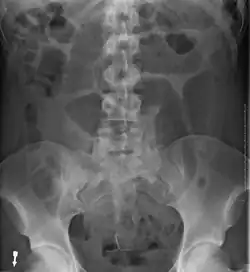

Diagnostic methodMedical imaging (plain X-rays, GI series, CT scan)[1]

Risk factors include a birth defect known as intestinal malrotation, an enlarged colon, Hirschsprung disease, pregnancy, and abdominal adhesions.[1] Long term constipation and a high fiber diet may also increase the risk.[3] The most commonly affected part of the intestines in adults is the sigmoid colon, with the cecum being the second most affected.[1] In children the small intestine is more often involved.[5] The stomach can also be affected.[6] Diagnosis is typically with medical imaging such as plain X-rays, a GI series, or CT scan.[1]

After taking a thorough history, the diagnosis of colonic volvulus is usually easily included in the differential diagnosis. Abdominal plain x-rays are commonly confirmatory for a volvulus, especially if a coffee bean sign is seen. These refer to the shape of the air-filled closed loop of the colon, which forms the volvulus. Should the diagnosis be in doubt, a barium enema may demonstrate a "bird's beak" at the point where the segment of proximal bowel and distal bowel rotate to form the volvulus.